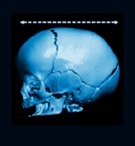

Importancia de la ecografía de suturas en el diagnóstico de deformidades craneales:

Leticia Gadea, Santiago Arriaga, Andrés García Bayce